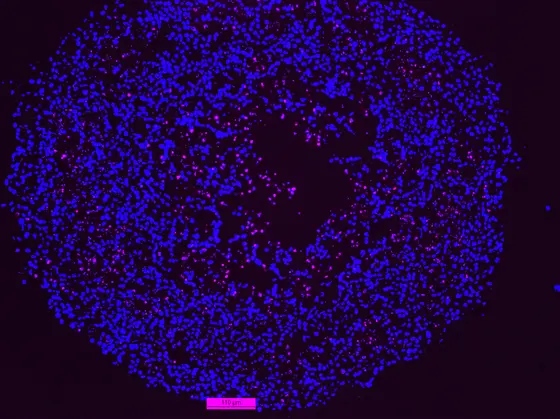

Im Inneren des Spheroids sterben Zellen am programmierten Zelltod Apoptose (pink)

Um in der Kulturschale die Mangelsituation im Inneren einer Krebsgeschwulst zu simulieren, ließen die Forscher die Krebszellen zu kleinen Gewebekügelchen (Spheroide) heranwachsen. Darmkrebszellen mit intaktem p53 passten sich an die Mangelbedingungen im Inneren der Spheroide an, indem sie ihr Wachstum drosselten. Die Tumorzellen mit p53-Defekt dagegen wuchsen unbeirrt weiter. Dabei kurbelten sie einen Stoffwechselweg an, der die Versorgung mit dem wichtigen Zellmembranbestandteil Cholesterin ermöglicht, den so genannten Mevalonat-Weg.

Der Mevalonat-Stoffwechselweg lässt sich mit Statinen, gängigen Cholesterin-Senkern, hemmen. Und tatsächlich: Statinbehandlung löste unter den Mangelbedingungen im Inneren der p53-defizienten Mini-Tumoren den programmierten Zelltod – Apoptose – aus. Dagegen reagierten Mini-Tumoren mit intaktem p53 nicht auf die Medikamente.